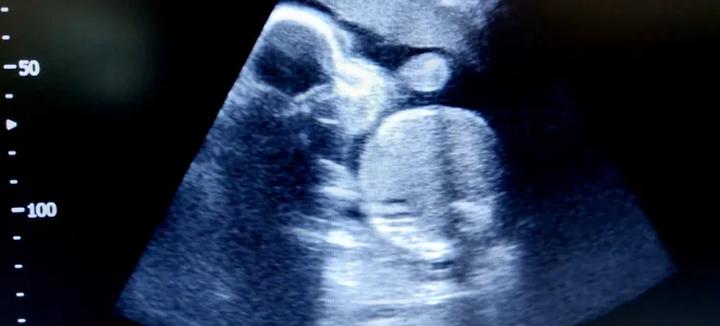

Nie zapomnij o badaniu połówkowym, które zbliża się wielkimi krokami. To magiczna chwila, gdy lekarz sprawdzi rozwój Twojego dziecka. Może również potwierdzi płeć? Jeśli nie chcesz wiedzieć, powiedz to przed badaniem. Nie ma żadnego ciśnienia! Potem, pełna radości, możesz myśleć o imieniu i kolorach dla malucha. Rozpocznij przygotowania na jego przyjście na świat. Osiemnasty tydzień ciąży to emocjonujący czas dla maluszka i mamy. Ciesz się każdą chwilą tej wyjątkowej podróży!

Wielki dzień badania i notowania wszystkiego, co zmienia się w małym ciele, nadchodzi! USG połówkowe to prawdziwa bitwa najlepszych lekarzy, którzy przyglądają się wszelkim detalom maluszka. Niczym detektyw Murdock, starają się zobaczyć każdy „ukryty znak”. Badają także, czy Twoja pociecha nie ma wad rozwojowych. Już wkrótce dowiesz się, jak czuje się Twój maluszek. Jeśli chcesz, poznasz również jego płeć. Mały szef czeka, aby ci o tym powiedzieć, musisz tylko wybrać idealne imię!

Badania prenatalne to bardzo ważny temat dla przyszłych mam. Możecie je traktować jak zdobywanie wiedzy z encyklopedii życia. Co warto wiedzieć? Po pierwsze, badania są dla Was, nie tylko dla lekarzy! Wyjątkowym doświadczeniem jest badanie połówkowe. Odbywa się ono w drugiej części ciąży, zazwyczaj między 18. a 22. tygodniem. To nie tylko potwierdzenie płci, ale także sprawdzenie, czy maluszek rozwija się prawidłowo. Przygotujcie się na emocjonujące chwile, gdy lekarz przygląda się główce, nóżkom i paluszkom!

Gdy nadejdzie czas badania połówkowego, możecie czuć lekkie zdenerwowanie. To zupełnie normalne! W końcu chodzi o wasze maleństwo. Może to być jak wizyta w kinie – czekacie na to, co się wydarzy. Podczas badania lekarz sprawdzi wiele parametrów. Na koniec z pewnością zapyta, czy chcecie poznać płeć dziecka. Tu pojawia się dylemat – chcieć wiedzieć, czy nie? Niektórzy rodzice wolą niespodziankę. Jak to bywa w życiu, każdy wybór jest dobry.